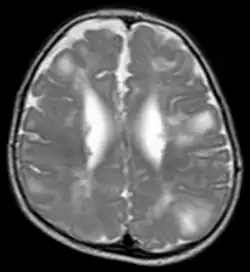

Classic intracranial manifestations of TSC include subependymal nodules and cortical/subcortical tubers.[6]

The tubers are typically triangular in configuration, with the apex pointed towards the ventricles, and are thought to represent foci of abnormal neuronal migration. The T2 signal abnormalities may subside in adulthood, but will still be visible on histopathological analysis. On magnetic resonance imaging (MRI), TSC patients can exhibit other signs consistent with abnormal neuron migration such as radial white matter tracts hyperintense on T2WI and heterotopic grey matter.

Subependymal nodules are composed of abnormal, swollen glial cells and bizarre multinucleated cells which are indeterminate for glial or neuronal origin. Interposed neural tissue is not present. These nodules have a tendency to calcify as the patient ages. A nodule that markedly enhances and enlarges over time should be considered suspicious for transformation into a subependymal giant cell astrocytoma, which typically develops in the region of the foramen of Monro, in which case it is at risk of developing an obstructive hydrocephalus.

A variable degree of ventricular enlargement is seen, either obstructive (e.g. by a subependymal nodule in the region of the foramen of Monro) or idiopathic in nature.

- A magnetic resonance imaging (MRI) of the brain to identify tubers, subependymal nodules (SEN) and sub-ependymal giant cell astrocytomas (SEGA).